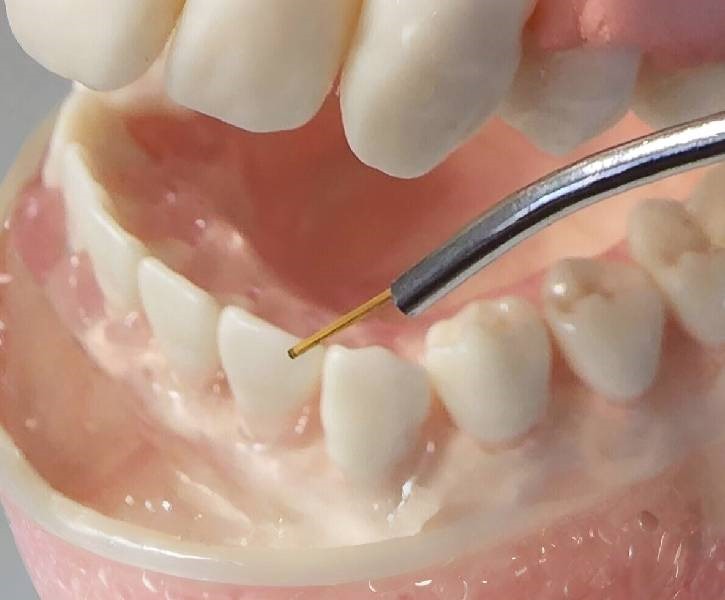

Traditional Gum Surgery

Traditional gum surgery is a time-tested approach used to treat more severe cases of gum disease or structural issues. It involves carefully removing diseased tissue and reshaping the gums for optimal oral health.